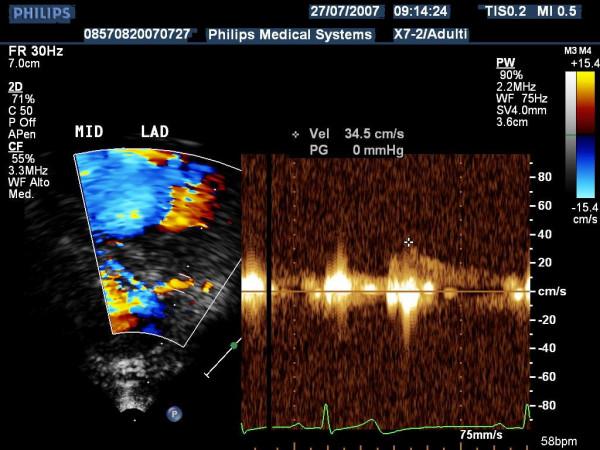

The aim of this paper is to highlight coronary investigation by transthoracic Doppler evaluation. This application has recently been introduced into clinical practice and has received enthusiastic feedback in terms of coronary flow reserve evaluation on left anterior coronary artery disease diagnosis. Such diagnosis represents the most important clinical application but has in itself some limitations regarding anatomical and technological knowledge. The purpose of this paper is to offer a didactic approach on how to investigate the different segments of left anterior and posterior descending coronary arteries by transthoracic ultrasound using different anatomical key structures as markers. We will conclude by underlining that, nowadays, innovative technology allows complete evaluation of both major coronary arteries in many patients in a resting condition as well as during pharmacology stress-tests, but we often do not know it.